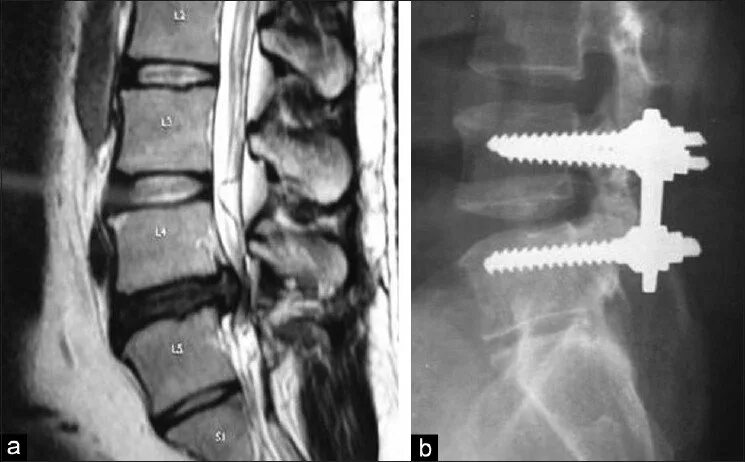

Операция удаление грыжи l5 s1